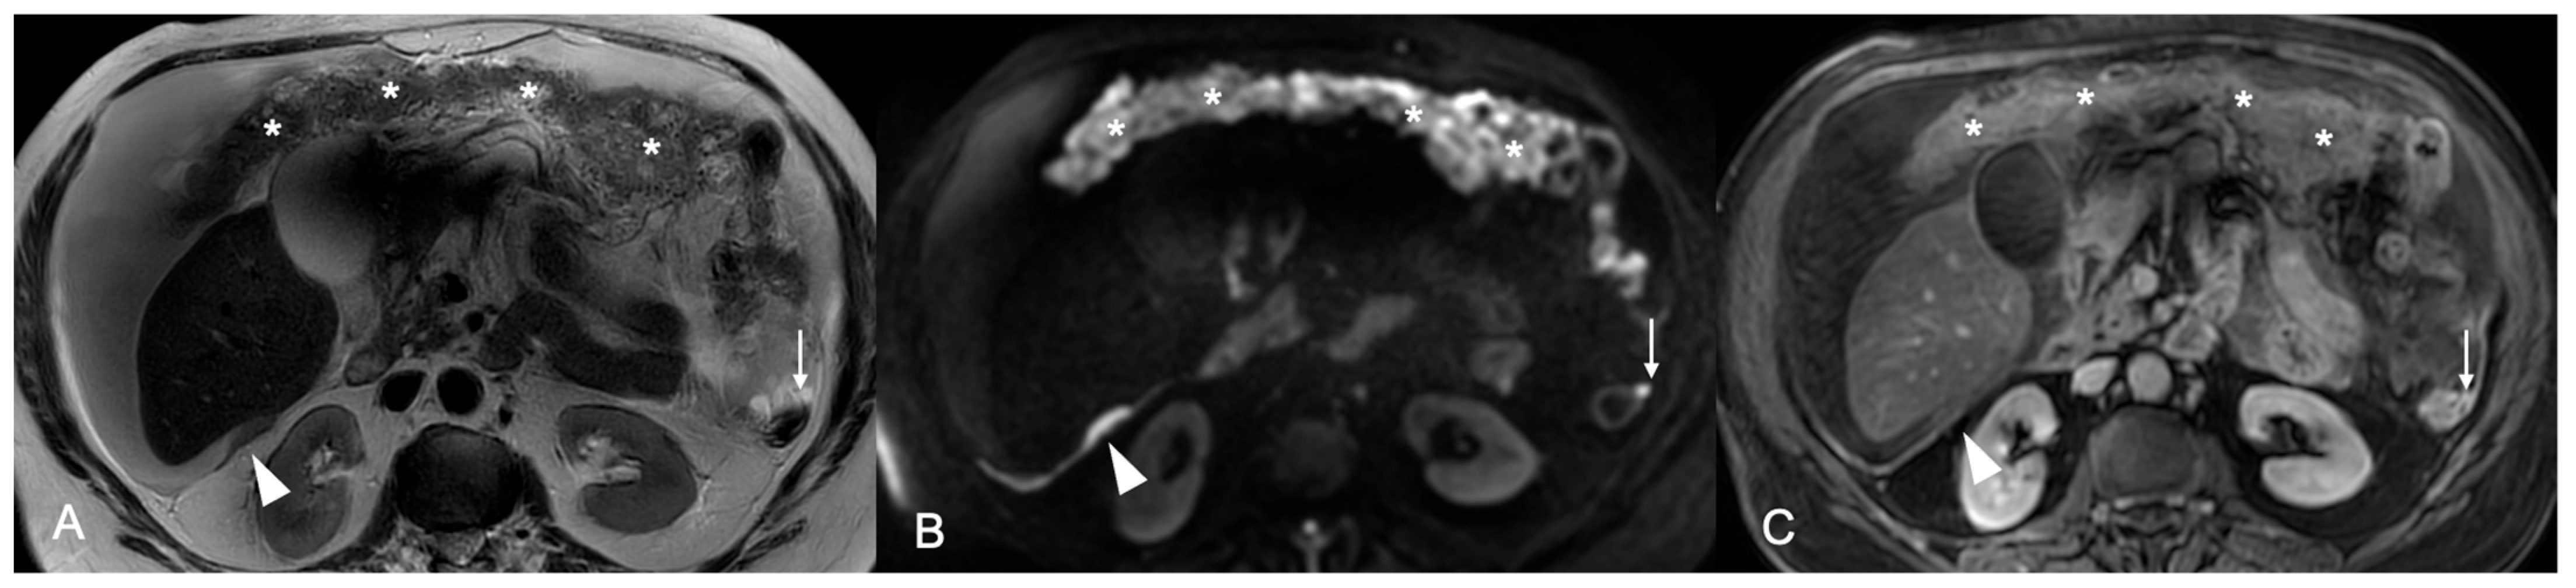

Background/Objectives: Cytoreduction status is a critical prognostic factor in ovarian cancer, yet preoperative selection of patients suitable for primary debulking surgery and accurate prediction of surgical outcome remain challenging. This study aimed to evaluate the prognostic ability of MRI-based Fagotti score and Peritoneal Cancer Index (PCI) for predicting resectability of peritoneal disease in ovarian cancer patients. Methods: This was a prospective single-center observational study. Patients with suspected primary ovarian cancer who underwent preoperative MRI of the abdomen and pelvis with a dedicated protocol were considered. MRI-based Fagotti score and PCI were determined by two readers independently, using a combination of T2W, Diffusion-Weighted Imaging (DWI), and contrast-enhanced T1W sequences. In cases of discordance, a third radiologist reviewed the scans and consensus was reached. ROC analysis and logistic regression were used to evaluate prognostic performance. The reference standard to predict resectability was optimal cytoreduction defined as residual disease ≤1 cm. Results: Forty-six women with epithelial ovarian cancer (mean age 56.3 ± 2.6 years) who underwent preoperative MRI, followed by laparoscopy and/or laparotomy, were included in the study. Both MRI-based Fagotti score and PCI showed high predictive value for predicting resectability (AUC 0.92 and 0.94, respectively). Optimal cut-offs were ≤6 for Fagotti score and ≤20 for PCI. Patients with scores below these thresholds had >60-fold (Fagotti) and >100-fold (PCI) increased odds for successful primary cytoreduction (p < 0.001). Conclusions: MRI-based Fagotti score and PCI may serve as powerful noninvasive predictors of surgical outcome in ovarian cancer. MRI may reliably guide treatment decisions, reducing unnecessary laparotomies and optimizing patient selection.